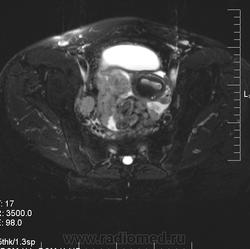

в-целом, cогласен. Карциноматоз тоже есть. Видится еще диффузный аденомиоз матки (задней стенки).

Мне кажется, что есть инфильтрация и передней стенки прямой кишки.